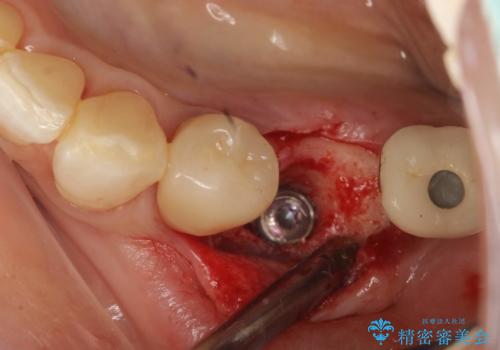

- 単独のインプラント補綴にて咬合の回復を計画した。

インプラント治療は、骨が十分になくてもさまざまな補助処置を行うことで可能になります。

インプラントの種類:straumann SLActive